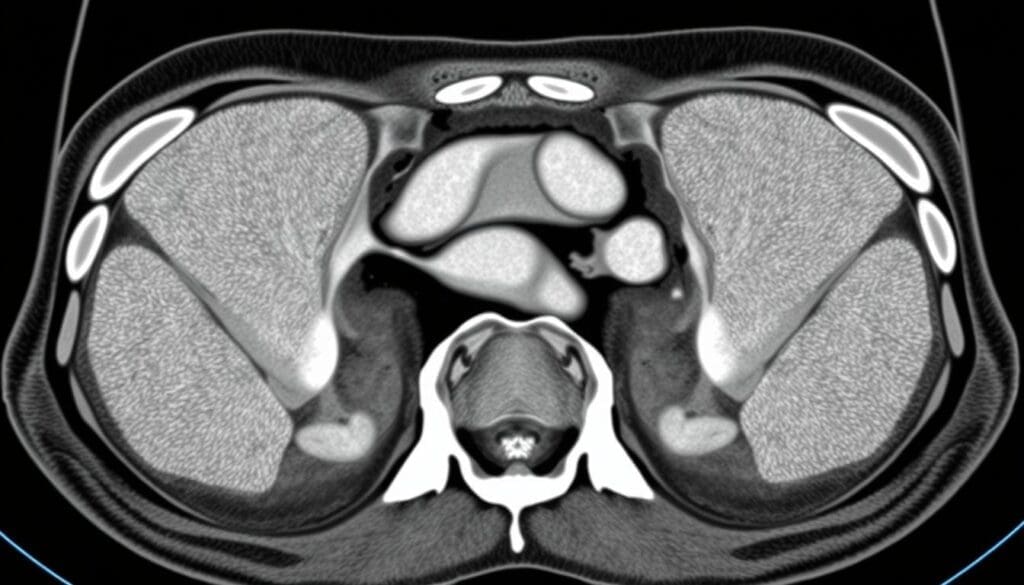

Will a CT Scan Show a Hernia? Accuracy Rates Explained

Understanding how well CT scans find inguinal hernias is key for everyone involved. We’ll look at what makes CT scans good and what they can’t do.

CT scans are key for spotting inguinal hernias when a simple check isn’t enough. They give clear pictures of the area, helping doctors see hernias well.

Specificity of CT Scans for Inguinal Hernias

Specificity means a test can tell who doesn’t have a disease. CT scans are very good at this, with a success rate of 92% to 98%. This means if a CT scan says you don’t have a hernia, it’s probably true.

A study in the Journal of the American College of Radiology found a 95% specificity rate. This is great for avoiding wrong surgeries and giving patients the right info.

Sensitivity Considerations

Sensitivity is about catching those who do have a disease. CT scans are good at showing who doesn’t have a hernia but not always at finding those who do. This is because small or hidden hernias can be missed.

Medical Expert, a radiologist, says CT scans are helpful but have limits. Studies show their sensitivity for hernias is 70% to 85%.

Many things can affect how accurate a CT scan is. These include the doctor’s skill, the equipment quality, and the patient’s body and health.

“The diagnostic accuracy of CT scans for inguinal hernias is generally high, but it’s not a perfect test. We need to consider both the imaging results and clinical findings when making diagnostic decisions.”

Medical Expert, Radiologist

In short, CT scans are very useful for finding inguinal hernias. But knowing their strengths and weaknesses helps us make better choices about health care.